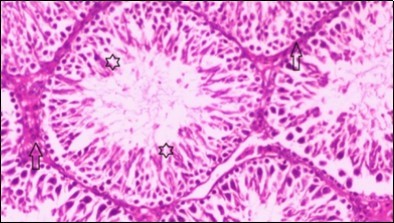

Testis Histopathological Observations

Histological examination of control rats' testis showed normal histological structure of the seminiferous tubules with an increase in the spermatogonia and other spermatocytes compared with the diabetic rats which showed an obvious decrease in the count of germinal cells generally and sloughing of germ cell in the lumen of seminiferous tubules in addition to absence of the mature sperms (Figure 3 and Figure 4). Rats tested of Fenugreek group and those treated with Glimepiride (Figure 5 and Figure 6) presented an increase in the number of spermatogenic cells and mature sperms with few focal necrotic cells. Whereas the combination therapy group showed normal histological structure of the seminiferous tubules with normal spermatogonia, presence of ledying cells and more mature of sperms (Figure 7). STZ reduced testosterone production, suggesting a decrease in the function of both Leydig (testosterone producing cell) and Sertoli (spermatogenesis) cells, which might be caused by a reduction in insulin secretion. These changes are probably due to increased Reactive Oxygen Species (ROS) production by accelerated Advanced Glycation End Products (AGE) formation 31 hexosamine and Protein Kinase C pathway. The administration of Fenugreek seeds to diabetic rats significantly decrease of sperm shape abnormality and improve the sperm count 32. Glimepiride reduced sperm abnormality and increased testis weights and sperm count by its antioxidant action 30. The potential protective efficacy of Fenugreek seed extract when added to Glimepiride was observed on reproductive systems.

Figure 4.Photomicrogragh of testis section of diabetic rat showing the sloughing of germ cells towards lumen of seminiferous tubules, absence of spermatozoa with low height of germinal epithelium and congested wide interstitial tissue (star). (H&E) (40x).

Figure 5.Photomicrogragh of testis section of treated rat with Fenugreek showing noticeable improvement with increased number of spermatogenic cells included moderate amount of spermatozoa (star) and organized Sertoli cells (arrow). Note liquid infiltration (dashed arrow) in wide interstitial tissue (H&E) (40x).